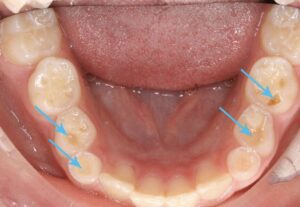

In some cases, a dental examination may be necessary to detect evidence of teeth grinding and jaw clenching, which can manifest as broken teeth and fillings, worn crowns, or cusps (the term used to describe the raised edge of a tooth), and sensitive jaw muscles. Additionally, sore muscles along the sides of the head and neck are rather prevalent.

Common signs: waking with jaw pain or headaches, flattened or worn tooth surfaces, chipped teeth, tooth sensitivity, and your partner hearing grinding sounds. Dr. Cohan can identify wear patterns during your exam.

Over time, grinding causes progressive tooth wear, cracked teeth, damaged dental work, TMJ disorders, chronic headaches, gum recession, and tooth loss. Early intervention with a nightguard prevents thousands in restorative treatment.